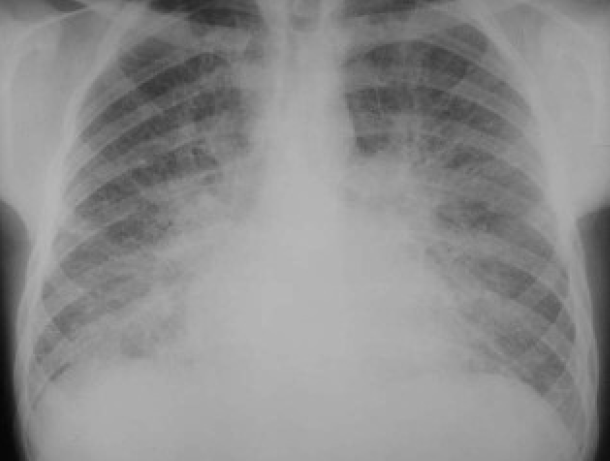

(a)胸片显示肺水肿.(b)ct显示小叶间隔增厚以及磨玻璃影

图片尺寸437x644

间质性肺水肿及轻度的肺泡肺水肿,双侧胸腔积液.

图片尺寸960x1280